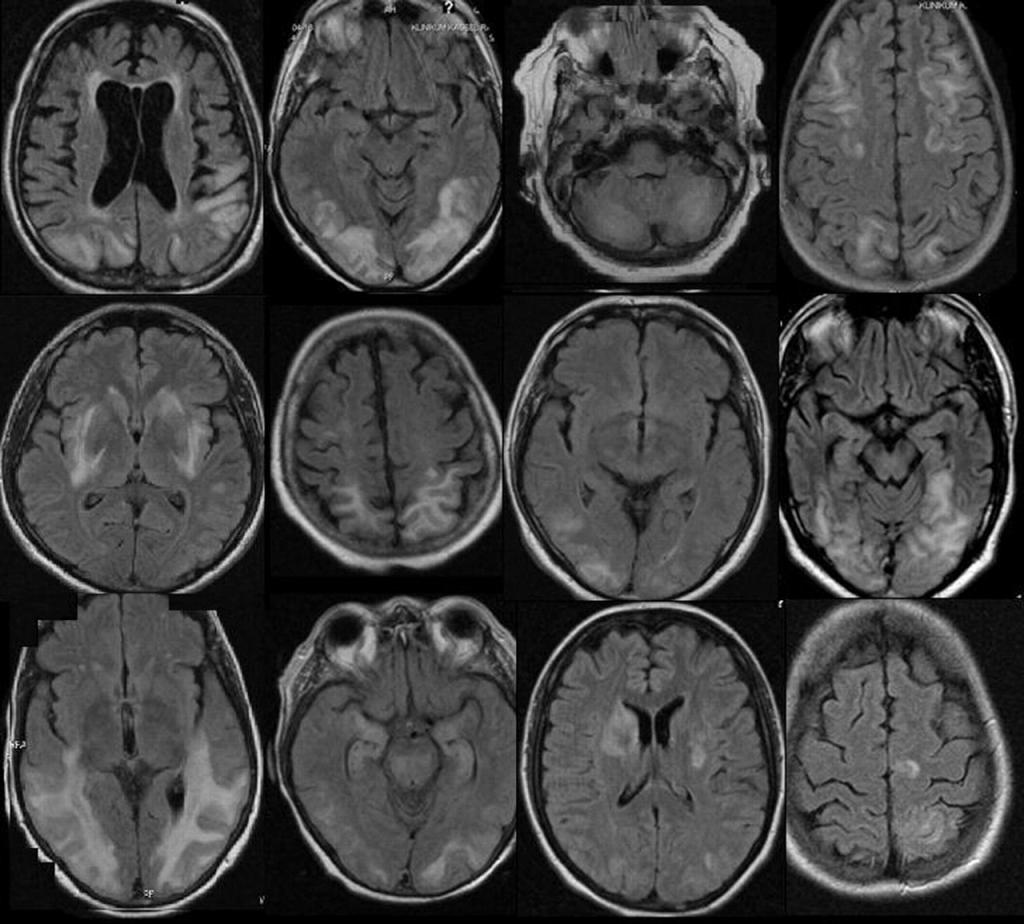

Основное отличие WB-MRI — возможность обследовать все тело целиком, выявляя патологии на ранних стадиях, которые иногда могут быть пропущены при локальных исследованиях․ Благодаря передовой технологии, WB-MRI применяется не только радиологами, но и кардиологами, онкологами, неврологами и специалистами по фтизиатрии в рамках комплексной диагностики․

- Высокая детализация: высокое качество изображений, способное выявлять мельчайшие изменения в тканях․

- Диагностика неврологических нарушений — выявление поражений головного мозга, спинного мозга, нервных структур․